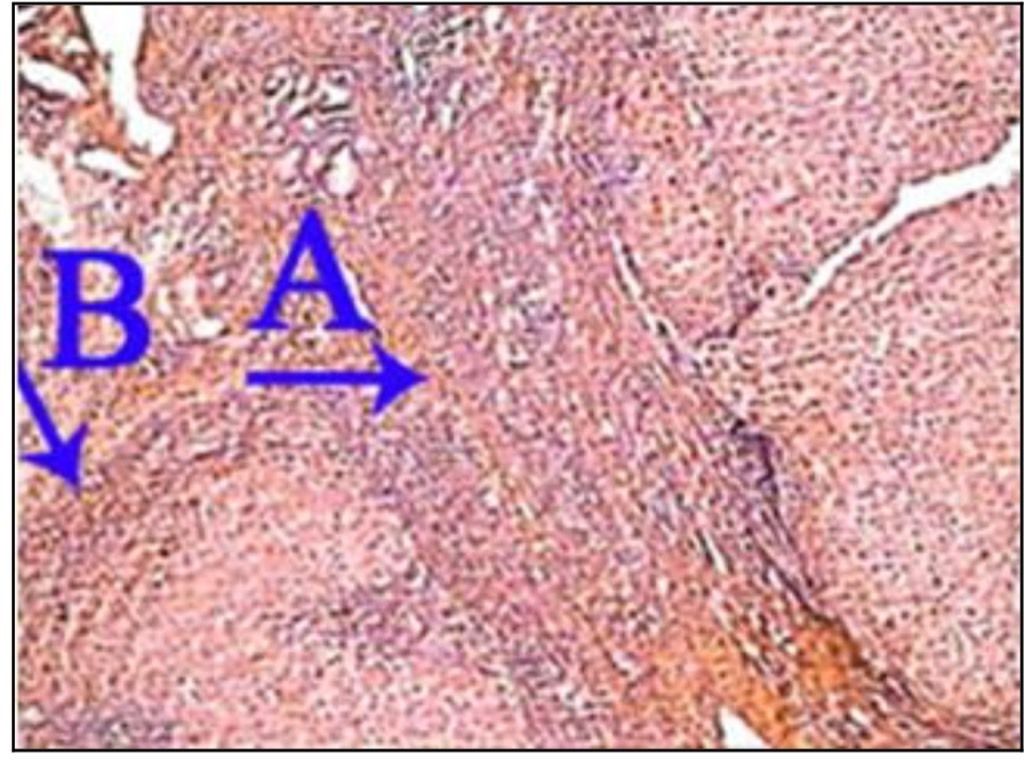

Question 11

Question

What is the correct answer at point A?

Answer

• - travées de sclérose annulaire

Question 12

What is the correct answer at point B?

• - nodule cirrhotique, sans veine Centro lobulaire

• - néoformation canalicule biliaire

• - infiltration lymphocytaire

• - hépatocyte contenant de la bile

Question 13

What is the correct answer at point C?